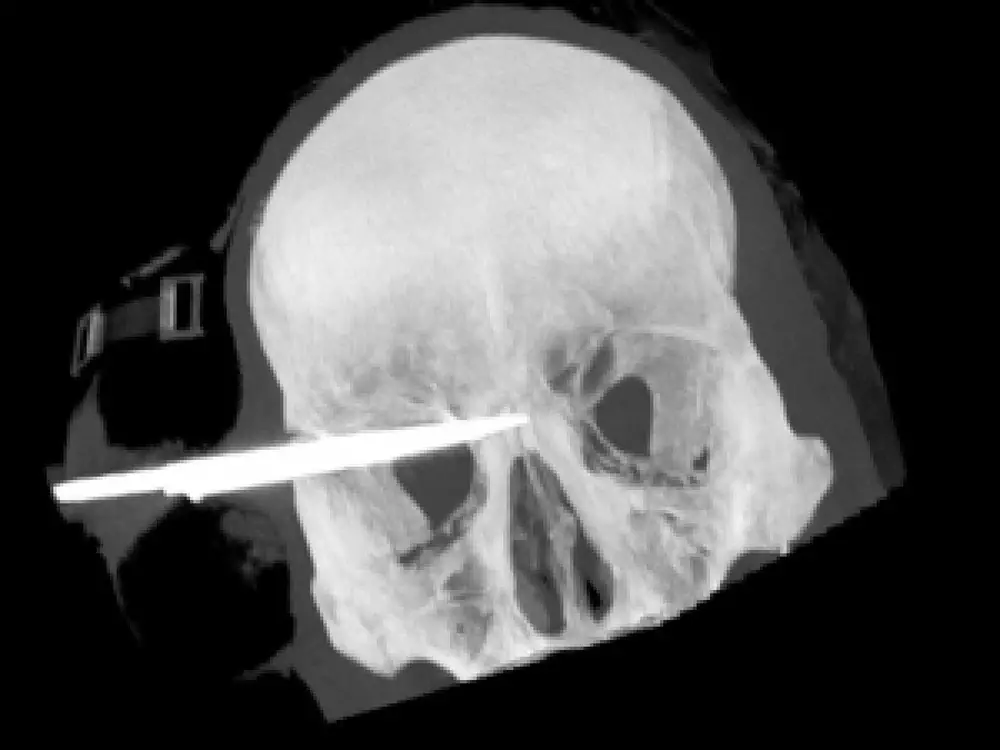

Новозеландец выжил после ранения в голову 9-сантиметровым ножом Предоперационный снимок. Фото с сайта tvnz.co.nz

20-летний житель Новой Зеландии выжил после ранения в голову 9-сантиметровым ножом, сообщает NEWSru.com. Уникальный случай в медицине подтверждает опубликованный в СМИ рентгеновский снимок. Инцидент произошел на вечеринке. Пострадавший молодой человек бросился разнимать драку, но сам получил ранение. На место приехал полицейский Карл Кристиансен, который раньше работал в реанимации. "Нож вошел прямо надо его левым глазом, и было видно только желтую ручку и около сантиметра лезвия. Я знал, что нож нельзя вынимать... Вообще ничего нельзя вынимать из человека, истекающего кровью", - рассказал полицейский. В больницу молодого человека доставили прямо с ножом в голове. Хирург Лесли Снэйп отметил, что только рентген помог оценить врачам сложность ситуации перед операцией. "Мы ожидали увидеть трехсантиметровое лезвие маленького ножа, не восемь сантиметров лезвия в голове. Все были в шоке", - сказал Снэйп. Отметим, что операция прошла настолько успешно, что пострадавший сохранил себе не только жизнь, но и зрение. Лезвие ножа прошло в двух миллиметрах от глазного яблока и в двух сантиметрах от головного мозга.